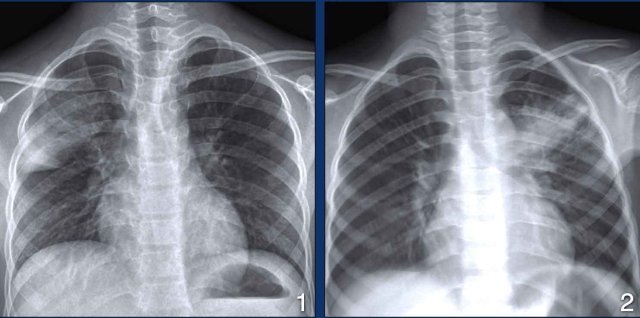

Now we know that the way TB presents on chest X-rays, mainly depends on the immune status of the patient.

In young children the immune response is less mature than in adults and TB disease more often presents with adenopathy, effusion and lower lung zone disease (figure right lung).

In adults with a competent immune system, TB more often presents with upper lobe consolidation and cavitation (figure left lung).

This also explains why in HIV-patients with a low CD-4 count lymphadenopathy, lower lobe consolidation and pleural fluid is more common, while in HIV-patients with a normal CD-4 count upper lobe cavitation is more common.